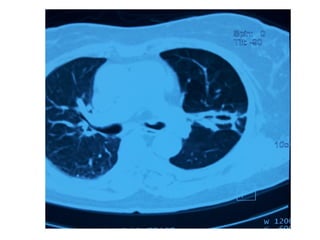

Case 2

• Mr V from Philippines was admitted in August

2013

• Fever

• Chest pain in Lt upper part of chest

• Pain is more with breathing

• Lost weight

• Productive cough

• Occasional hemoptysis

• Febrile 39.5 ⁰

• HR 112 bpm

• RR 22 breaths/min

• Chest : left bronchial breath sounds, pleural rub

• CVS and abdomen: Unremarkable

• CXR

• CBC

• Electrolytes

• Sputum AFB +ve

• PCR for MTB + ve

Case 2 • MrV from Philippines was admitted in August 2013 • Fever • Chest pain in Lt upper part of chest • Pain is more with breathing • Lost weight • Productive cough • Occasional hemoptysis

• Febrile 39.5⁰ • HR 112 bpm • RR 22 breaths/min • Chest : left bronchial breath sounds, pleural rub • CVS and abdomen: Unremarkable • CXR • CBC • Electrolytes • Sputum AFB +ve • PCR for MTB + ve